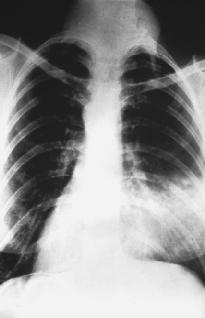

X ray showing pneumonia in the right lung. (Reproduced by

permission of the

National Audubon Society Collection/Photo Researchers, Inc.

)